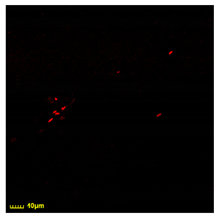

3.8. Relationship Between Diagnosis and Phagocytic Activity of Macrophages

The relationship between the patients’ diagnostic results and the phagocytic activity of macrophages was analyzed (Figure 8). The proportion of bacterial cells associated with CD206 + macrophages from the BALF was affected by the presence of mannan, a competitive ligand for CD206 mannose receptors, which play a key role in bacterial phagocytosis by macrophages. In the absence of mannan, E. coli W3110 exhibits a relatively high level of bacterial phagocytosis, approximately 10%, for all of the patient categories. However, the presence of mannan (the CD 206 concurrent ligand) strongly inhibits bacterial binding by macrophages in cases of pneumonia, in which macrophages overexpress CD206 receptors.

Figure 8.

Correlation analysis of the phagocytic activity of CD206+ macrophages in BALF against different bacterial cells, depending on the presence or absence of mannan, a competitive ligand for CD206 receptors.

Bacillus subtilis, by its nature, is less efficiently phagocytized compared to other bacteria. However, in the context of pneumonia, macrophages exhibit an increased phagocytic response towards these bacteria, which is also specifically suppressed by mannan.

Lactobacillus fermentum exhibits low binding in cases of asthma or pneumonia. Conversely, the markedly higher binding observed in the PCD group could suggest a potential divergence in the sensitivity of macrophages towards this specific type of bacteria, potentially due to an impairment in the functioning of immune system cells.

The data presented herein reveal a complex interplay between diagnostic markers and the phagocytic activity of macrophages. Notably, in acute inflammatory conditions such as pneumonia and acute bronchitis, a heightened level of phagocytosis is observed for E. coli and B. subtilis, with mannan exerting a significant inhibitory effect on binding. Conversely, in cases involving structural alterations in the lung tissue, such as pulmonary cavitary disease (PCD) and bronchiectasis, there appears to be a shift in macrophage activity, leading to their active engagement with normal bacteria, specifically L. fermentum, while a lesser effect of mannan is observed.